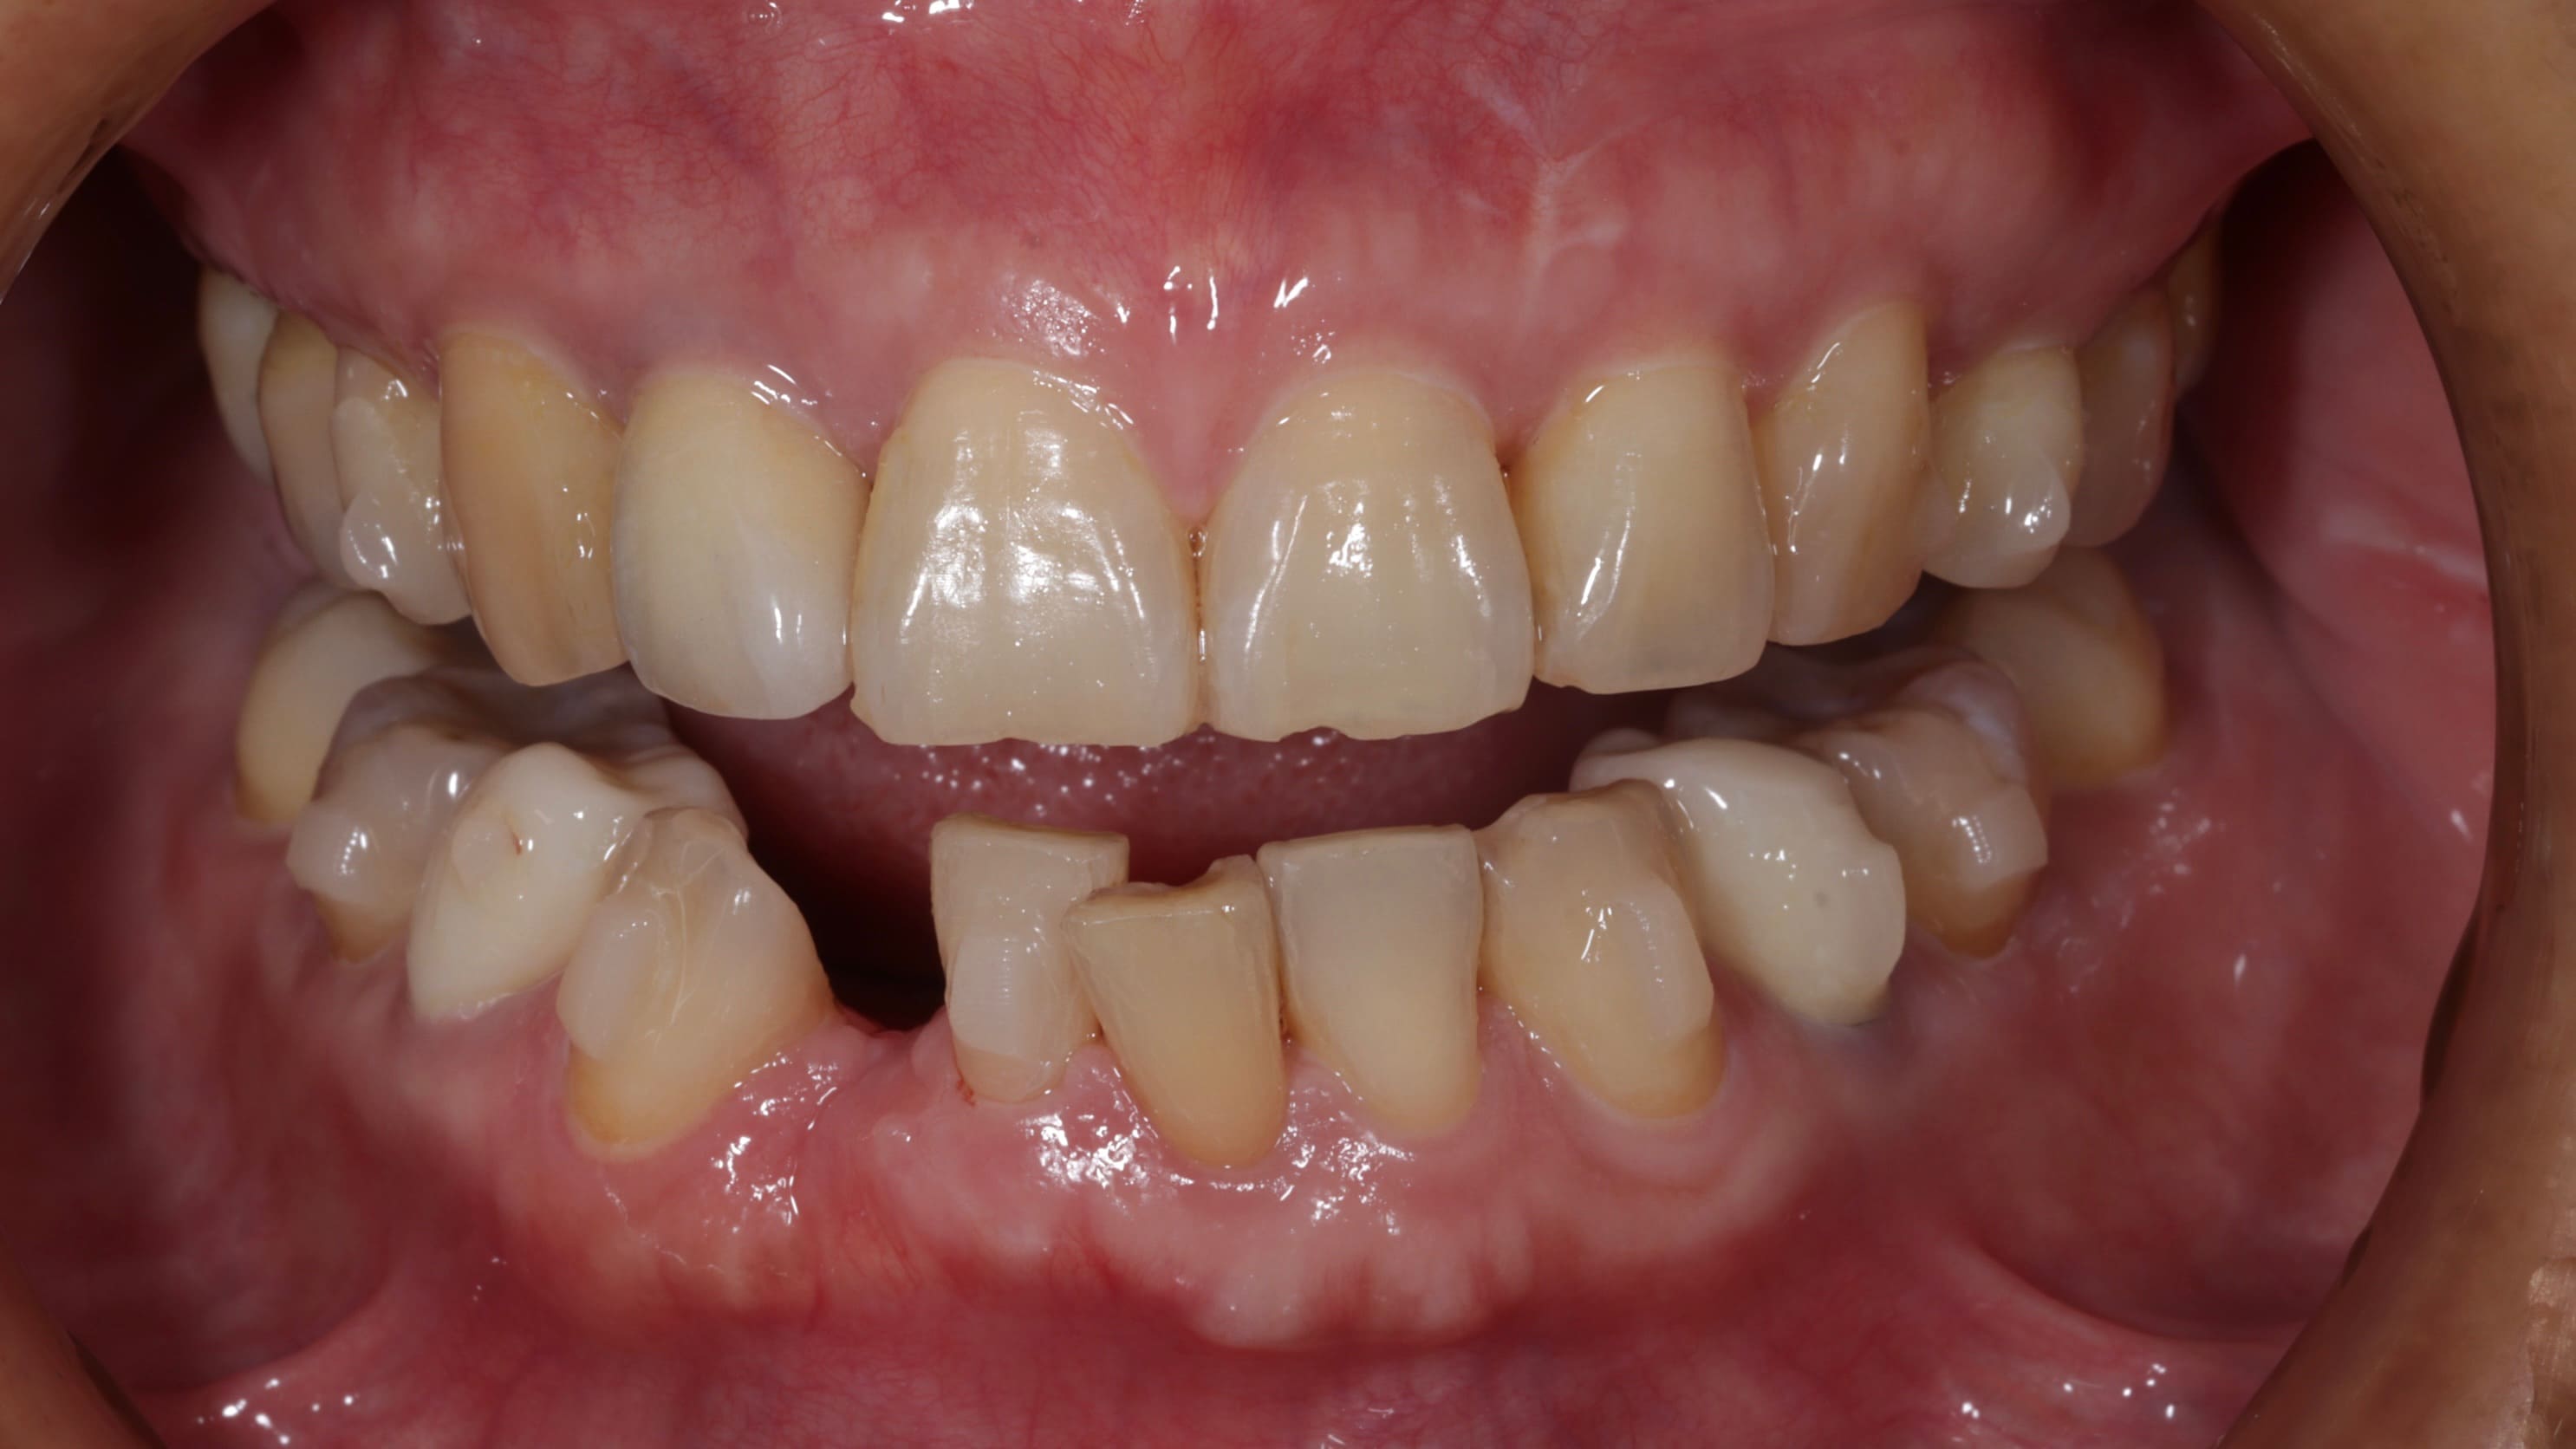

首先是 牙齒排列不整,她年輕時曾接受過矯正治療,但因為沒有持續佩戴維持器,導致牙齒在不知不覺間位移,不僅影響外觀,也讓日常清潔變得困難。再來是 牙周病問題,雖然患者有在其他診所進行治療,但由於右下側有一顆牙齒搖晃得非常厲害,牙周破壞的情況相當嚴重,原本的醫師告知她可能無法保留。最後是 舊假牙美觀不佳 的問題,患者的右上側門牙曾做過植牙治療,但牙套的角度讓牙齒看起來有些傾斜,並非正對前方,視覺上顯得不協調。此外,口內還有一些早期製作的舊牙套,邊緣都露出黑黑的金屬邊,每次張嘴說話都感到不自在。

第三階段:拔除無法保留的牙齒,重建骨頭基礎

搖晃嚴重的左下側門牙,經過我們仔細檢查評估後,發現牙周組織破壞真的太多,如果勉強保留,反而會影響到整個口腔的穩定性。與患者仔細說明後,最終決定拔除這顆牙齒,並同時進行補骨修復,重建骨頭根基,就能夠在後續治療中透過矯正方式關閉拔牙造成的空隙,不需要再進行額外的植牙手術。